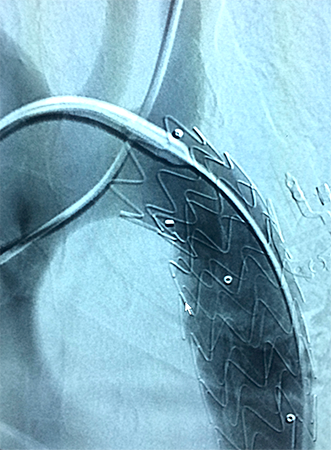

Cirurgia de Aneurisma de Aorta

Chamamos de aneurisma de aorta, a dilatação exagerada deste vaso. A doença pode acometer qualquer porção da aorta, desde sua saída do coração, até seu final, à altura do umbigo. Os aneurismas de aorta mais frequentes estão localizados no abdome, especialmente abaixo das artérias renais. Há basicamente duas formas de correção a fim de evitar a ruptura do aneurisma: a cirurgia e a correção endovascular com implante de uma endoprótese (assista ao vídeo). Na cirurgia para correção do aneurisma de aorta abdominal, com anestesia geral, o abdome é aberto pelo cirurgião vascular e o segmento dilatado da aorta é substituído por uma prótese tubular artificial, que se integra perfeitamente ao paciente.

Cirurgia endovascular

- Tratamento com cateteres e guias

- Implante de stents e endopróteses

- Menor trauma cirúrgico